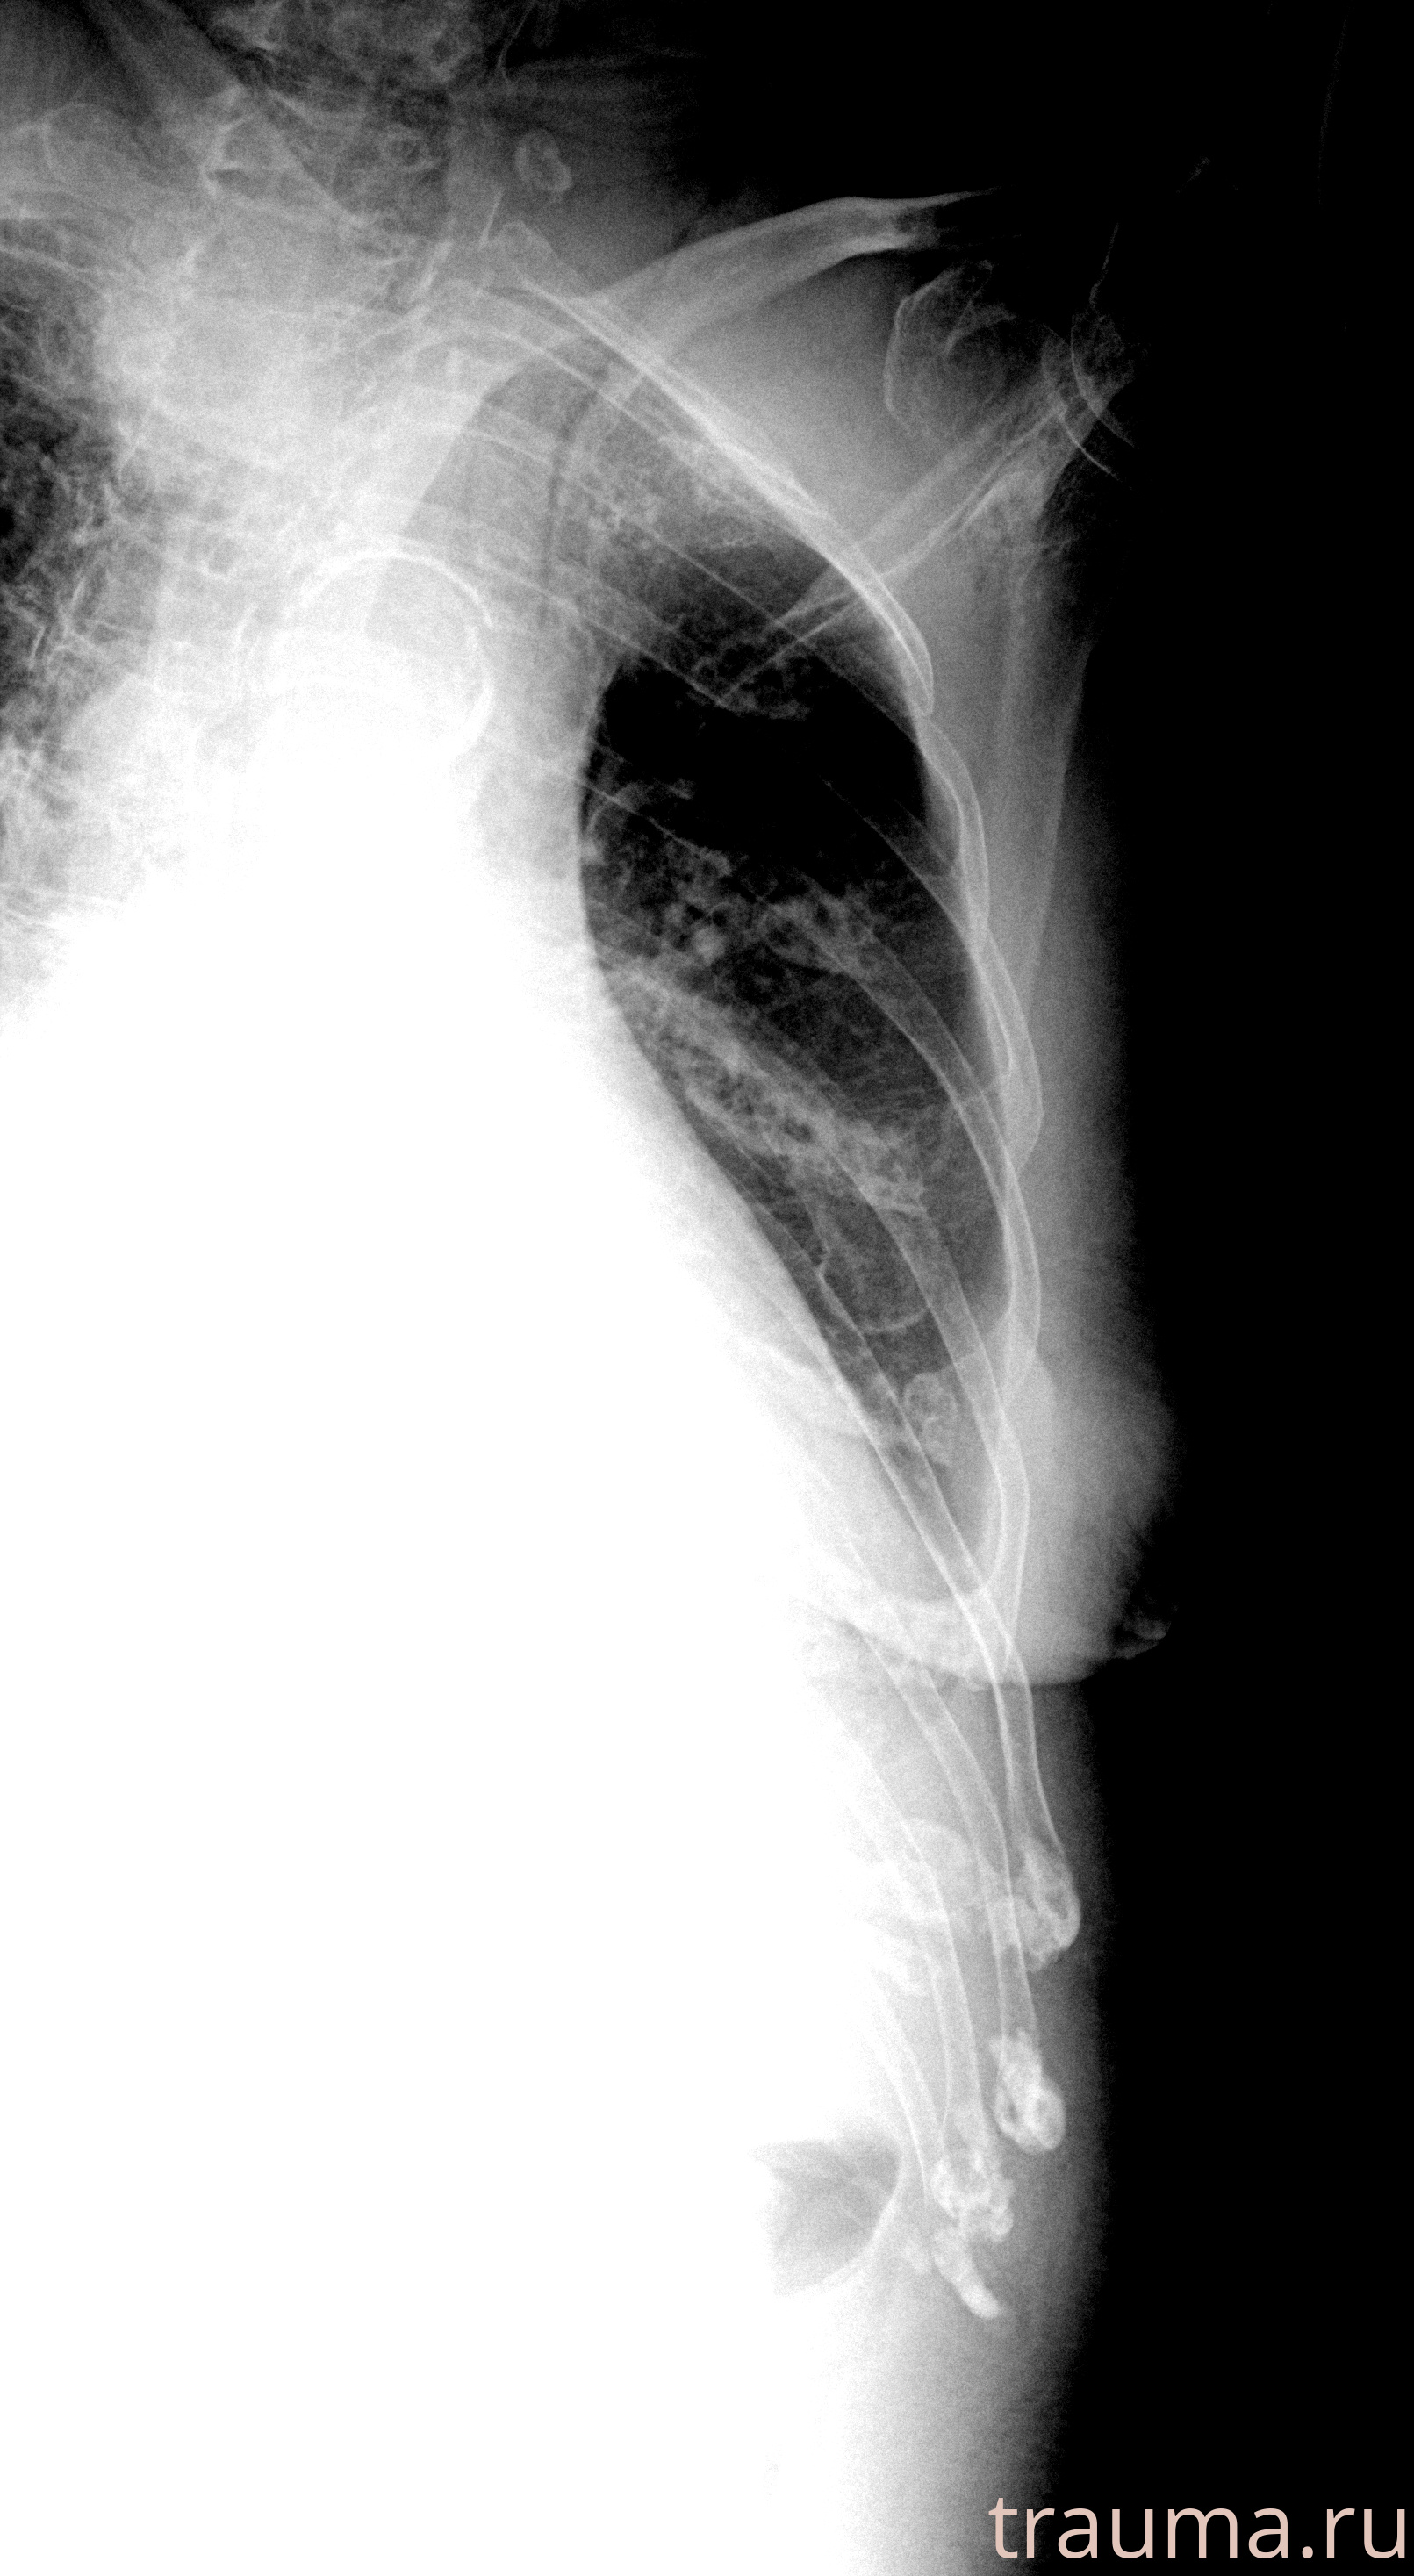

Рентгенограммы

Рентген на дому: по вашему адресу приезжает врач-рентгенолог, травматолог-ортопед с мобильным рентгеновским аппаратом, проводит диагностику травмы или заболевания, делает необходимые рентгенограммы, дает рекомендации по дальнейшему лечению. Получить качественные снимки в домашних условиях возможно благодаря уникальной методике, разработанной МосРентген Центром для института  Склифосовского

при переломе шейки бедра и пневмонии от компании МосРентген Центр - партнера Института имени Склифосовского